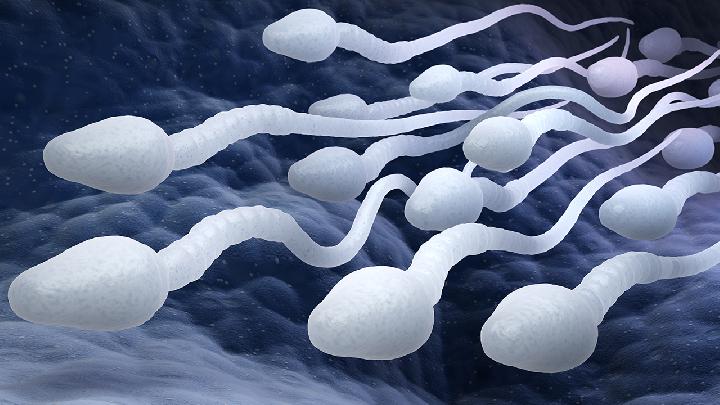

医院数字区 - 不孕不育 - 男性不育 - 男性不育 - 危害

得男性不育的危害有哪些

1、影响夫妻感情:男性不育若得不到及时的治疗,从而使得夫妻性生活不能得到和谐,使夫妻双方的感情逐渐变得冷淡,严重危害了夫妻感情状况。 2、丧失自信:如果男性患有不育,总是感觉身体不行,造成压力过大,使患者逐渐丧失信心,在心理上产生障碍,恶性循环,后果不堪设想。 4、家庭破裂:若早泄导致不育的话,在性生活中,妻子的性欲得不到满足,并长时间失去了性生活的兴趣,导致积怨越来越多,影响患者的家庭,甚至导致家庭破裂。 生活中在患有男性不育后就会让男性失去做爸爸的可能,因此人们应该极力避免此病的出现才对,这对男性而言是非常重要的。而受到一些因素影响,患病的人是越来越多了,这样也是让危害普遍存在,不仅影响到了正常的生活质量,还有可能会破坏个人的家庭,是非常不利的,希望大家可以注意到这些。 关于影响的信息 大家对于酒糟鼻疾病了解不是很多,酒糟鼻在生活中很常见,是属于皮肤病的一种,酒糟鼻疾病出现以后,对患者的生活带来很大影响,许多朋友因此而感到非常沮丧,接下来让专家给我们详细的介绍一下,酒糟鼻产生的危害有哪些,酒糟鼻会不会影响患者的寿命呢?  在胃溃疡中,尤其是男性的亲属中,其发病率高于一般人,有时可见到一些家族中的几代人都有消化性溃疡,分居两地的双生子同患本病的事例也偶有发现,揭示本病可能与遗传有关。溃疡病发病既受环境因素影响,又受遗传因素影响,是一种多基因遗传性疾病。但是,此病在生活上多加注意是预防的关键。  得了白塞氏病寿命会受到影响吗?白塞氏病是一种慢性免疫系统病,由于很多患者对该病比较陌生,因此对于它可能造成的危害和影响并不清楚,甚至有些人因为病症轻微,根本就不把疾病放在心上,白塞氏病病症多,危害巨大,严重者甚至可以导致死亡,影响着患者的寿命,因此,广大患者一定要引起足够的重视。  坐骨神经痛是指沿坐骨神经分布区域,以臀部、大腿后侧、小腿后外侧、足背外侧为主的放射性疼痛。而坐骨神经痛早期症状一般表现为下肢疼痛、麻木等,那么许多患者会问:“坐骨神经痛会影响寿命吗?”专家表示:坐骨神经痛是不会直接影响到人的寿命的,请看下面的介绍:  糖尿病足会造成什么影响呢?这个问题是很多糖尿病足患者都想了解的,清楚了解这个就会更加重视糖尿病足这种病,很多糖尿病足患者就是不了解这个病,才导致了严重的后果的,下面我们就来了解下糖尿病足会造成什么影响。  软组织受到损伤影响是非常大,不仅会影响到患者正常生活,因此带来更多的困扰,所以患上软组织损伤的情况下就需要积极到正规做详细检查,了解目前情况,更好的针对性治疗,同时不行患上软组织损伤患者也非常想知道会不会因此而影响寿命问题,下面我们来详细了解得软组织损伤影响寿命吗?  强迫症属于焦虑障碍的一种类型,是一组以强迫思维和强迫行为为主要临床表现的神经精神疾病,其特点为有意识的强迫和反强迫并存,一些毫无意义、甚至违背自己意愿的想法或冲动反反复复侵入患者的日常生活。那么,强迫症会影响患者寿命吗?  吸烟有害健康这是大家耳熟能详的事了,很多的疾病也是通过吸烟而引起的,而糖尿病这种疾病也不例外,很多糖尿病肾病患者都是烟民,这些朋友认为吸烟对内脏器官有影响,那么下文我们就来了解下糖尿病足患者吸烟有哪些影响?  甲状腺癌患者有些情况下医生会建议做整个切除手术,那么这些做了切除手术的患者真的就可以治愈吗,切除了对身体没有影响吗,会不会影响寿命呢,今天就这个问题我们来带大家了解一下,甲状腺癌整个切除对寿命有影响吗?  前置胎盘就是在女性孕期中的胎儿没有完全覆盖在子宫上的一种现象。相信不少人对前置胎盘的了解不是很多,其实大家是应该多了解前置胎盘的护理措施的,从而才能更好的对前置胎盘患者进行护理,特别是前置胎盘患者更应该多加了解。准妈妈应注意前置胎盘的影响,对于前置胎盘应该学会它的护理措施,下面我们就来看一下吧。  小儿麻痹症是多见于儿童时期的一种疾病,孩子在患上小儿麻痹症以后,他们的腿部就会丧失行走的能力,给他们带来非常严重的伤害,这种疾病是一种极其难以治疗的疾病,小儿麻痹症很可能对寿命有影响,危害也很大,接下来小编为朋友们介绍一下小儿麻痹症的危害。 |